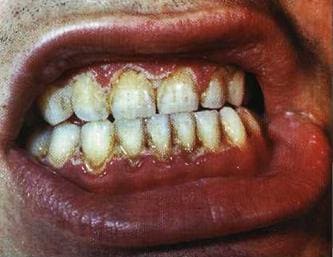

Фото Гингивит

Десны при пародонтите, как правило, воспалены, кровоточат, может быть гнойное отделяемое из десневых карманов.

Отличительным признаком при пародонтите является образование, помимо мягкого зубного налета, так называемого твердого зубного налета или зубного камня.

Если оставить без внимания и это состояние, происходит полное разрушение кости, удерживающей зуб. Как следствие, при пародонтите возникает подвижность зубов, происходит «оголение» корней зубов.